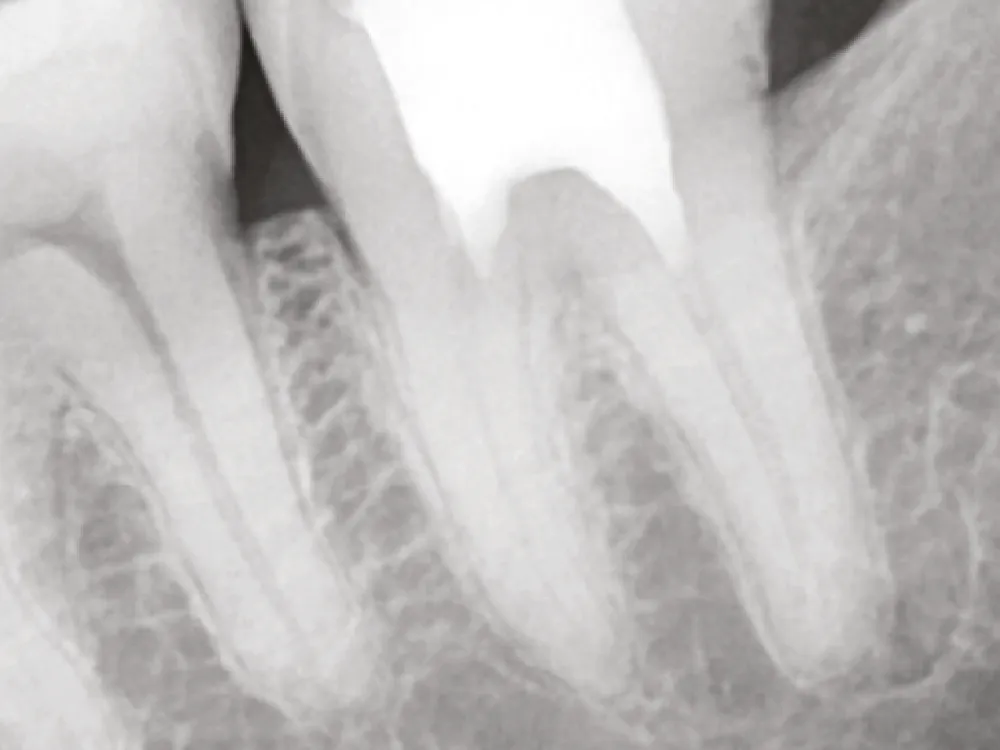

Cas clinique

Dr. Ju-Kyung Lee

1

Avant le traitement

2

Application du One-Fil Putty Injectable

3

Après le traitement